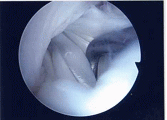

外側円板状半月損傷

外側円板状半月損傷は水平断裂で始まり、強い症状に発展したときは複合断裂になっていることが多くなります。長期経過例では変形性変化を合併することが多くなります(Okazaki 2006)。このタイプの半月板は切れ始めたら正常にできるだけ近い半月板に形成します。手術は関節鏡手術で手術翌日に松葉杖なしで退院出来ます。

完全型円板状半月遊離縁

右:円板状半月